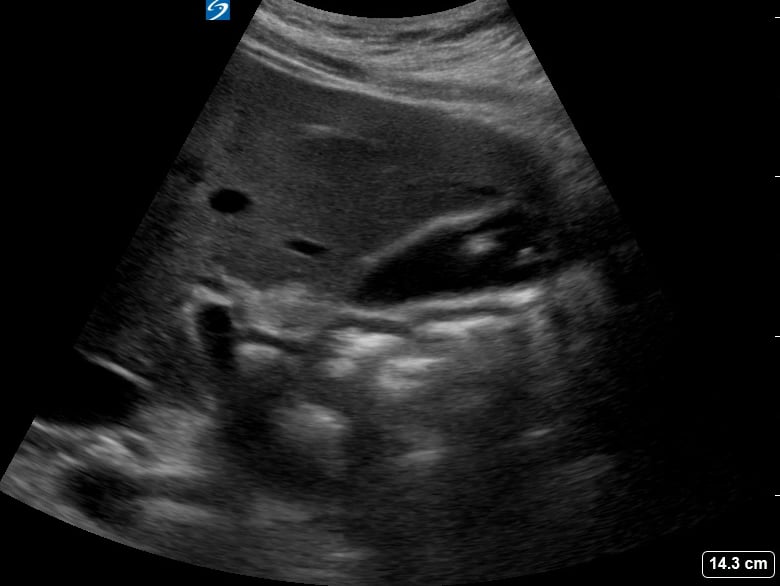

Gallstones are hardened deposits of digestive fluid that can form in the gallbladder, a small organ beneath the liver. In abdominal ultrasound, these concretions appear as hyperechoic structures within the gallbladder lumen, often with posterior acoustic shadowing. Their presence is a common finding during abdominal scans, frequently associated with symptoms like right upper quadrant pain, nausea, and vomiting, particularly after fatty meals.

Medical ultrasound plays a crucial role in diagnosing gallstones and related conditions such as cholecystitis (gallbladder inflammation) or choledocholithiasis (gallstones in the bile duct). Sonographic evaluation helps assess their size, number, and mobility, guiding clinical management and treatment decisions for patients experiencing abdominal discomfort or suspected biliary tract pathology.